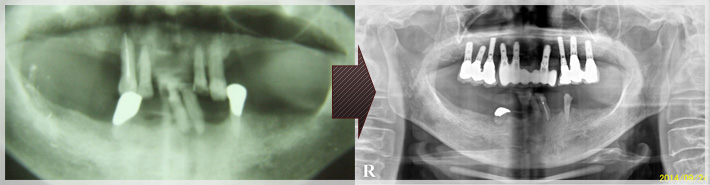

| 治療前後パノラマ |

インプラント治療 症例のご紹介4 S様 上顎へ3本 下顎へ4本埋入の事例

こちらは上顎がインプラント3本を埋入、

下顎へインプラント4本を埋入した事例 となっております。

| 治療前 | 治療後 上3本 下4本埋入 |